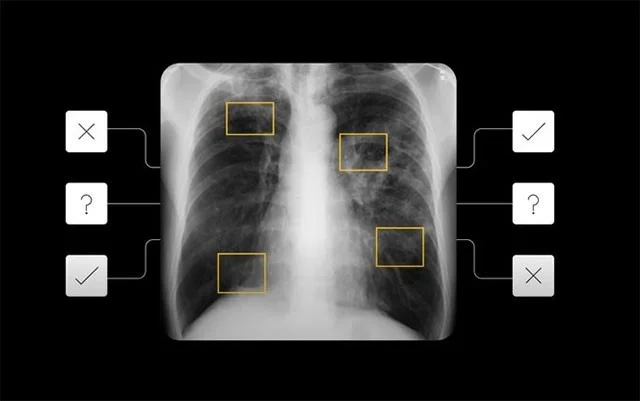

Google, tüberküloz için yüksek riskli vakaları erken tespit etmek, hastalara daha derinlemesine öneriler ve takip testleri önermek için derin öğrenmeyi kullanıyor. Bu model esas olarak göğüs röntgenlerini ön tarama adımı olarak kullanıyor ve yüksek risk faktörleri tespit edilirse sistem tavsiyede bulunarak hastanın bir uzmana görünmesini öneriyor. Bu, röntgen filmleri aracılığıyla akciğer tüberkülozu için bir "hızlı test" sistemi olarak anlaşılabilir.

Mühendisler bu yapay zeka sistemini oluşturmak için dokuz farklı ülkeden kimliği belirsizleştirilmiş verileri kullandılar ve ardından bunu beş farklı ülkedeki vakalar üzerinde test ettiler. Google, şirket içi testlerinde modelinin 14 radyologun sonuçlarına benzer oranda yanlış pozitif ve yanlış negatif sonuçlar döndürebileceğini söyledi. Klinikler, bu teknolojiyi kullanarak ek testlere ihtiyaç duyulması halinde önerilen eşikleri belirleyebilir ve böylece daha doğru tanı sonuçlarına ulaşabilirler.